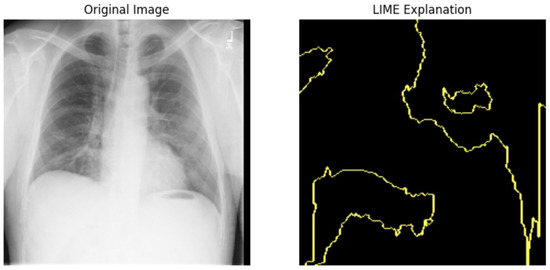

5.4.1. Local Interpretable Model-Agnostic Explanations for Clinical Validation

We applied scientific analysis on a random 7 sample, which was provided by the clinical specialist. The LIME Analysis for Image Data (a), (b), (c), (d), (e), and (f) is in Figure 22, Figure 23, Figure 24, Figure 25, Figure 26 and Figure 27. There are two parts of LIME analysis from the provided chest X-ray images to detect the disease area. Original Image and LIME explanation;

• Original Image: The patient’s thoracic cavity. It displays the typical anatomical structures of the chest, including the lungs, ribs, and heart.

• LIME Explanation: The result of applying LIME to the chest X-ray image. The yellow boundaries indicate the regions of the image that were most influential in the model’s decision-making process when determining whether the image indicated a particular condition. In this context, these regions are the parts of the X-ray that the AI model considered most important for making its diagnostic prediction.

The analysis very useful for clinicians to understand the model’s behavior and ensure that it aligns with medical expertise. The use of LIME helps in making the AI model’s interpretability decisions more transparent and interpretable. It allows medical professionals to verify whether the AI’s focus areas correspond to clinically significant regions. It also enhanced diagnostic capability of understanding which parts of the images in the AI model in refining the model further and ensures that it makes accurate and reliable predictions. This is particularly crucial in medical diagnostics where interpretability and accuracy are paramount.

Figure 22. LIME Analysis for Image Data (a) on original image to LIME explanation.